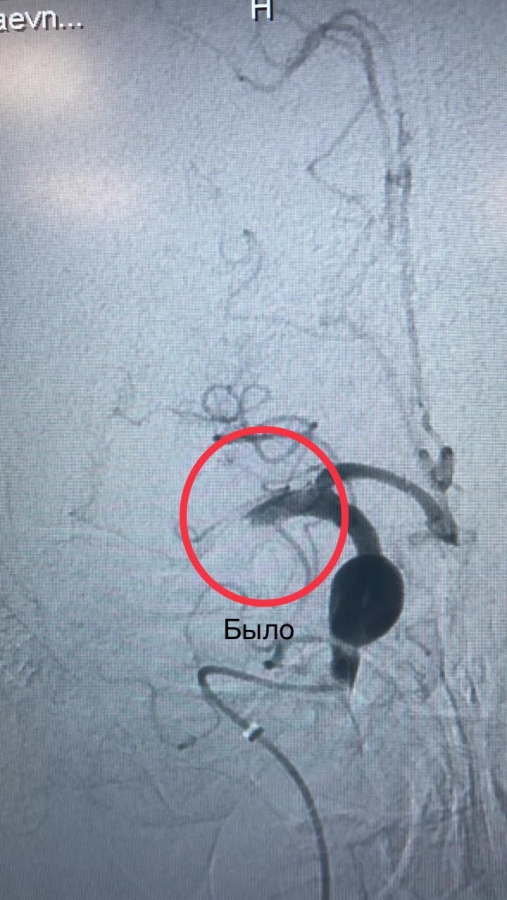

В саратовской областной клинической больнице (ОКБ) растет количество операций при ишемическом инсульте, который проводятся эндоваскулярным методом. О работе регионально-сосудистого центра (РСЦ) сообщили в телеграм-канале медицинского учреждения.

Как отметили медики, для оказания высокотехнологичной медицинской помощи при ишемическом инсульте по полису обязательного медицинского страхования в 2023 году ОКБ получила 50 квот (в 2022 году их было 8).

В больнице рассказали о двух таких операциях, пациенты которых поступили 9 августа с острым нарушением мозгового кровообращения (ОНМК).

«Одна из них, Елена, утром зашла в переполненный автобус и почувствовала себя плохо. Больше она ничего не помнит, проснулась женщина уже в реанимации после того, как наши врачи провели ей процедуру тромбоэкстракции (методика извлечения тромба при помощи специальных инструментов из наиболее крупных артерий головного мозга)», – написали медики.

Вторая женщина, по словам сотрудников ОКБ, поступила в одну из городских больниц Энгельса, где ей сделали тромболизис (введение препарата, растворяющего тромб), после чего незамедлительно направили в нашу больницу, как ведущее медицинское учреждение по лечение больных с ОНМК.

«Лечение инсульта – это прежде всего командная работа, она начинается от кареты скорой помощи, продолжается приёмным отделением, неврологами, врачами лучевой диагностики, лаборатории, эндоваскулярными хирургами, реаниматологами. Это слагаемые успешного исхода заболеваний наших пациенток», – отметил руководитель РСЦ Алексей Лобанов.

В настоящее время обе пациентки чувствуют себя удовлетворительно, двигательные и речевые функции полностью восстановились. Но, как отметил невролог Сергей Курносов, доли везения в подобных ситуациях, к сожалению, совсем немного. Гораздо важнее то, что пациенткам оказали своевременную медицинскую помощь в течение первых 2-3 часов после сосудистой катастрофы.